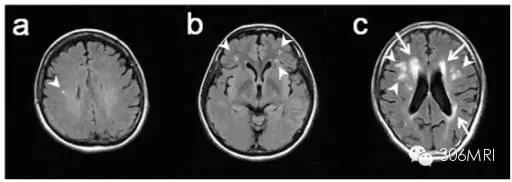

FLAIR扫描LA脑白质脱髓鞘改变

LA是多种原因引起的广泛的室周白质损害,与急性LACI病灶在常规MR检查中表现的信号强度相似,在通常遇到的老年患者中是个鉴别的难点,应用弥散加权成像DWI及ADC值可以较好地甄别急性LACI。